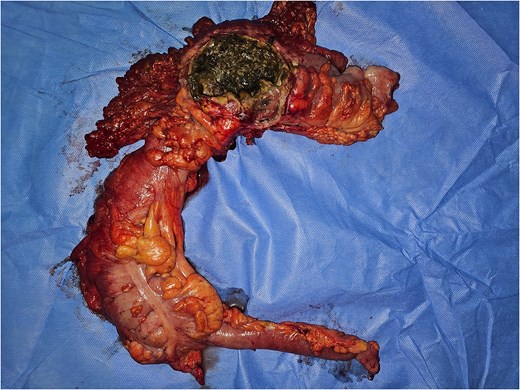

Emergency laparotomy revealed a large sealed perforation of the mid-transverse colon adherent to the first jejunal loop and omentum, purulent peritoneal effusion, and a fibrotic, inflamed duodeno-pancreatic block. The remainder of the gastrointestinal tract was unremarkable. A right extended hemicolectomy with double stoma, retroperitoneal lavage, and multiple drainages was performed (Figs 3–6).

Intraoperative image showing the thickened and infiltrated appearance of the transverse colon with a perforation contained by the omentum and the first ileal loop.

Intraoperative image showing the perforation of the middle third of the transverse colon.

Image of the surgical specimen of a right hemicolectomy showing the perforation.